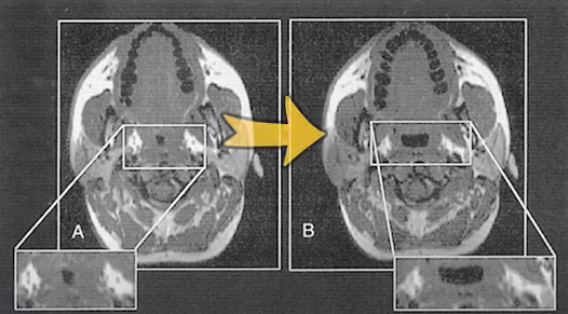

그렇게 하지 않았을 때는 자고 나면 기도가 전체적으로 좁아지는 것이 관찰이 되었는데, 자기 한 시간 전에 30분 정도 하체 운동을 했을 때는 기도가 잘 유지가 되는 것을 확인했습니다.